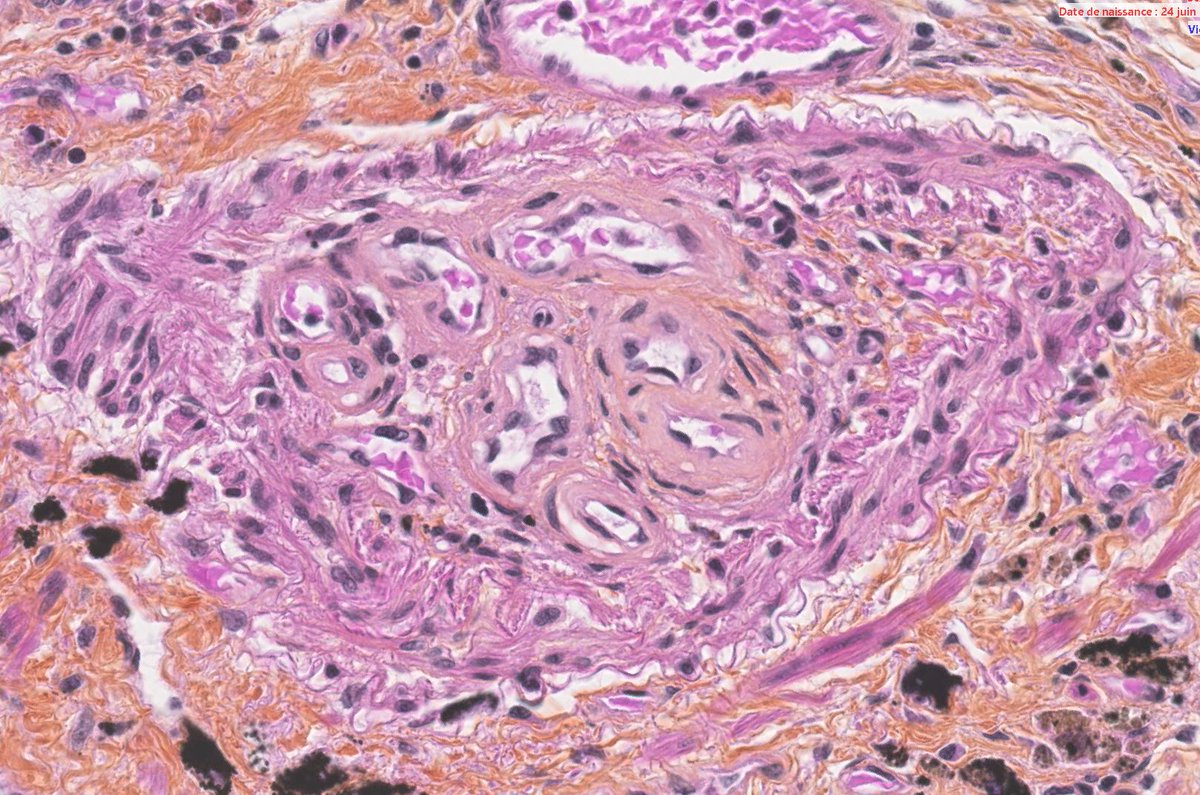

Thanks to all who engaged! Although uncommon, chronic LCH can lead to severe secondary pulmonary HTN which is what we see here. A spectrum of arterial lesions, including plexiform, dilatation, and medial hypertrophy. Wishing the patient a new lease on life with new lungs!

Explants from woman in her mid 40s. Clinical history on req: pulmonary hypertension. IHC is CD1a. Unifying diagnosis?